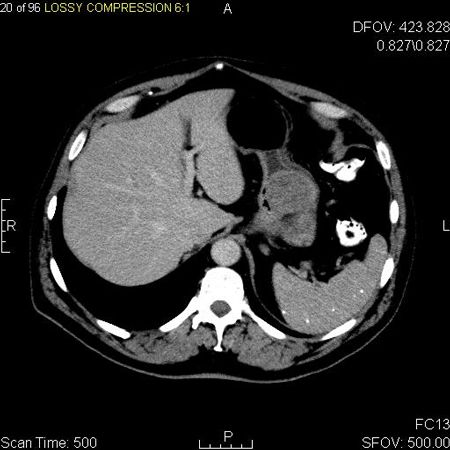

Axial contrast enhanced CT image of a gastrointestinal stromal tumor in the fundus of the stomach; source: Jto410, Wikimedia Commons